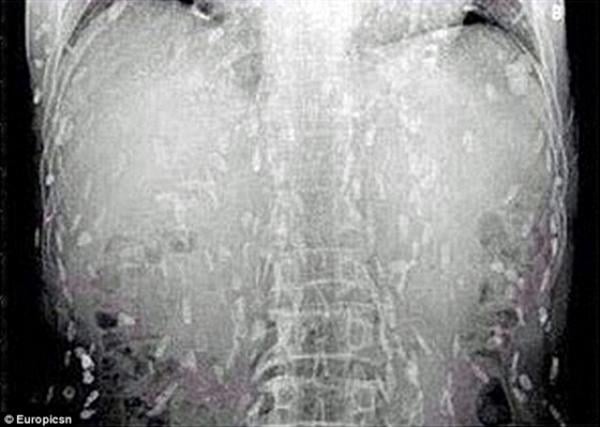

وكان الرجل ذهب إلى الطبيب يشكو من ألم في المعدة وحكة في الجلد، وكشفت الأشعة أن جسمه بالكامل أصيب بعدوى الدودة الشريطية .